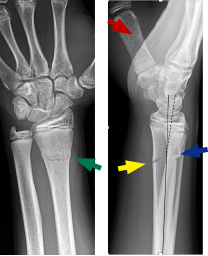

Radiograph Of Torus Fracture Of Distal Radius Anterior Posterior And Download Scientific Diagram